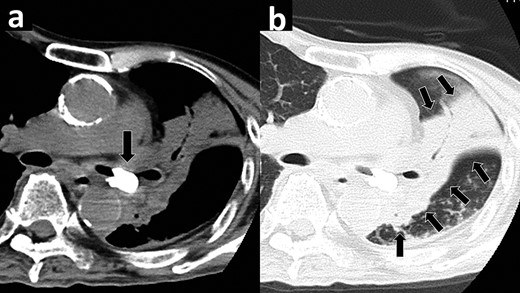

A 72-year-old man, bedridden with aphasia because of a medical history of stroke, was referred to our hospital because of high fever and hypoxemia. Chest X-ray and chest computed tomography (CT) demonstrated a 12- × 17-mm foreign body, in the left main bronchus, which appeared to be a tooth from its shape and high-density equivalent to that of a bone (Fig. 1a, arrow). The bronchial wall in contact with the foreign body was hypertrophic, and the left lung showed broad atelectasis (Fig. 1b, arrows). Laboratory studies revealed elevated values of white blood cell (15 600/μL) and C-reactive protein (12.62 mg/dL).

Chest computed tomography showing a bone density foreign body (arrow) in the left main bronchus (a). The left lung showing broad atelectasis (arrows) (b).